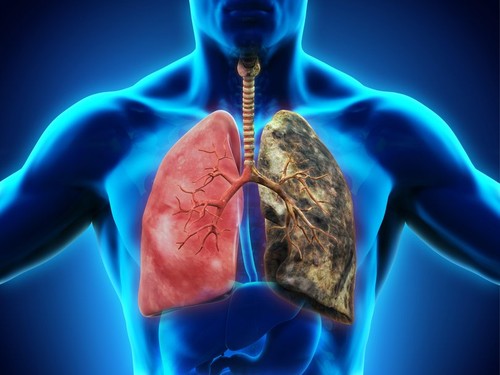

Prepoznavanje razlika između raka pluća kod pušača i nepušača od ključne je važnosti za uspešno lečenje. Naučnici su razvili personalizovane metode terapije koje su usmerene na specifične molekularne promene povezane sa rakom pluća kod nepušača.

Na primer, nepušači imaju veću verovatnoću da razviju adenokarcinom, vrstu raka pluća koja se takođe naziva sitnoćelijski rak pluća.

Ova vrsta raka karakteriše se sporijim rastom i može se prikazivati drugačije na medicinskim snimcima.

Grudni hirurg dr Danijel Bofa je razliku objasnio na sledeći način:

— Ako ste pušač, svoja pluća možete zamisliti kao vrećicu belih klikera, a rak je kao da tamo stavite crni kliker. Vrsta raka nepušača je više poput mrlje ili kvržice, više je kao maglovito područje.